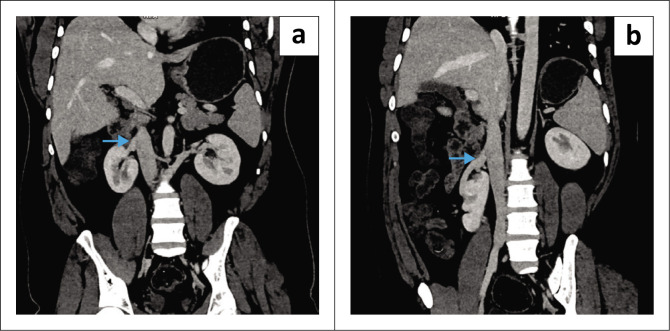

Supernumerary kidney (SK) is an uncommon anomaly of the urinary tract, usually occurring on the left side. A rare case of a partially-fused, SK on the right side is presented. The diagnosis is made through the identification of a distinct pelvicalyceal system along with its supplying renal artery and vein, utilising ultrasound, CT, or MRI.

Contribution: Correct diagnosis of partially-fused, supernumerary kidneys based on imaging is crucial to avoid unnecessary procedures, so that asymptomatic cases are managed conservatively.